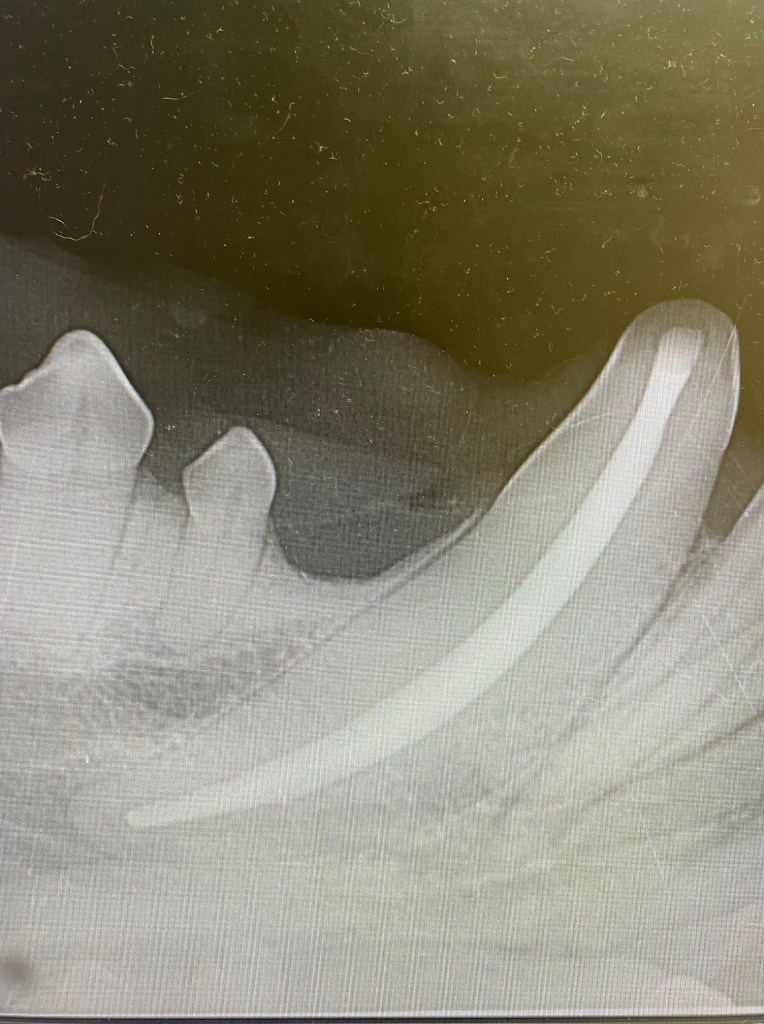

The above x-ray is an example of a young dog with a root apex that HAS closed. The dentine and periodontal ligament can be seen all the way around the apex of the tooth. This dog is likely just over 12-15 months old. A root canal CAN be done on this tooth as there is a “stopper” or end to the pulp cavity that will contain the substance used to fill the canal. There is also periapical lysis indicating infection is present.